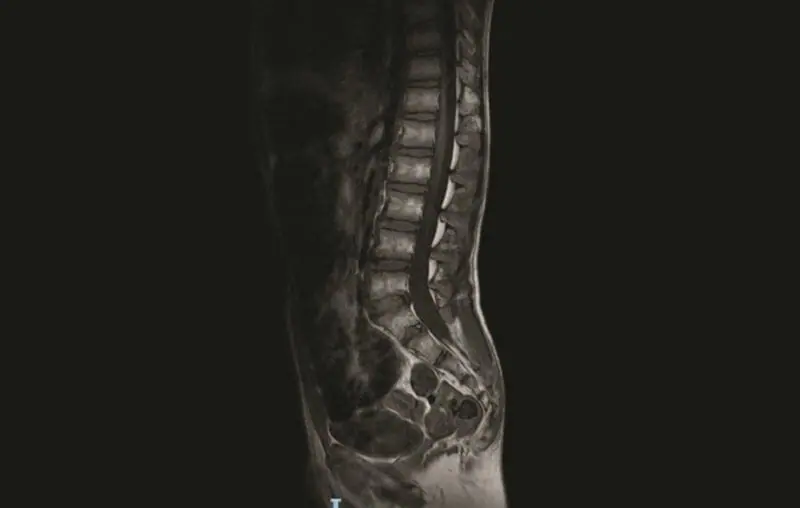

肌肉呈低紧张性,皮下组织不良。患者表现为踝关节瓣膜狭窄,膝关节挛缩,龙骨胸,肩胛翼,腕关节松弛和腹直肌痉挛。 发育迟缓,言语非常重。步态不稳定。髌骨骨性坏死反射消失不合格。收缩期小鼠2/6Levine突出,超声心动图证实存在心房间隔缺损并伴有肺动脉瓣狭窄。常规实验室分析电解质、血浆和尿液氨基酸、甲状腺标志物、有机酸、血浆嘌呤和转铁蛋白等电点电力电泳显示有左侧停留睾丸,总胆固醇在正常范围内。清醒和睡眠时的脑电图是正常的。用扩散强调成像序列的脑磁共振成像法(MRI)显示,脑膜下和脑膜上结构和脑室的体积和解剖结构都很规则。脊柱MRI检查发现,S5后弓部有裂隙,S3至S5的骶骨远端有脂肪肿症,右侧S2有一个Tarlov型的小包膜囊肿(见图1、2)。

图1 脊柱磁共振图像显示S5后弓部有裂隙,骶骨远端有脂肪瘤病。